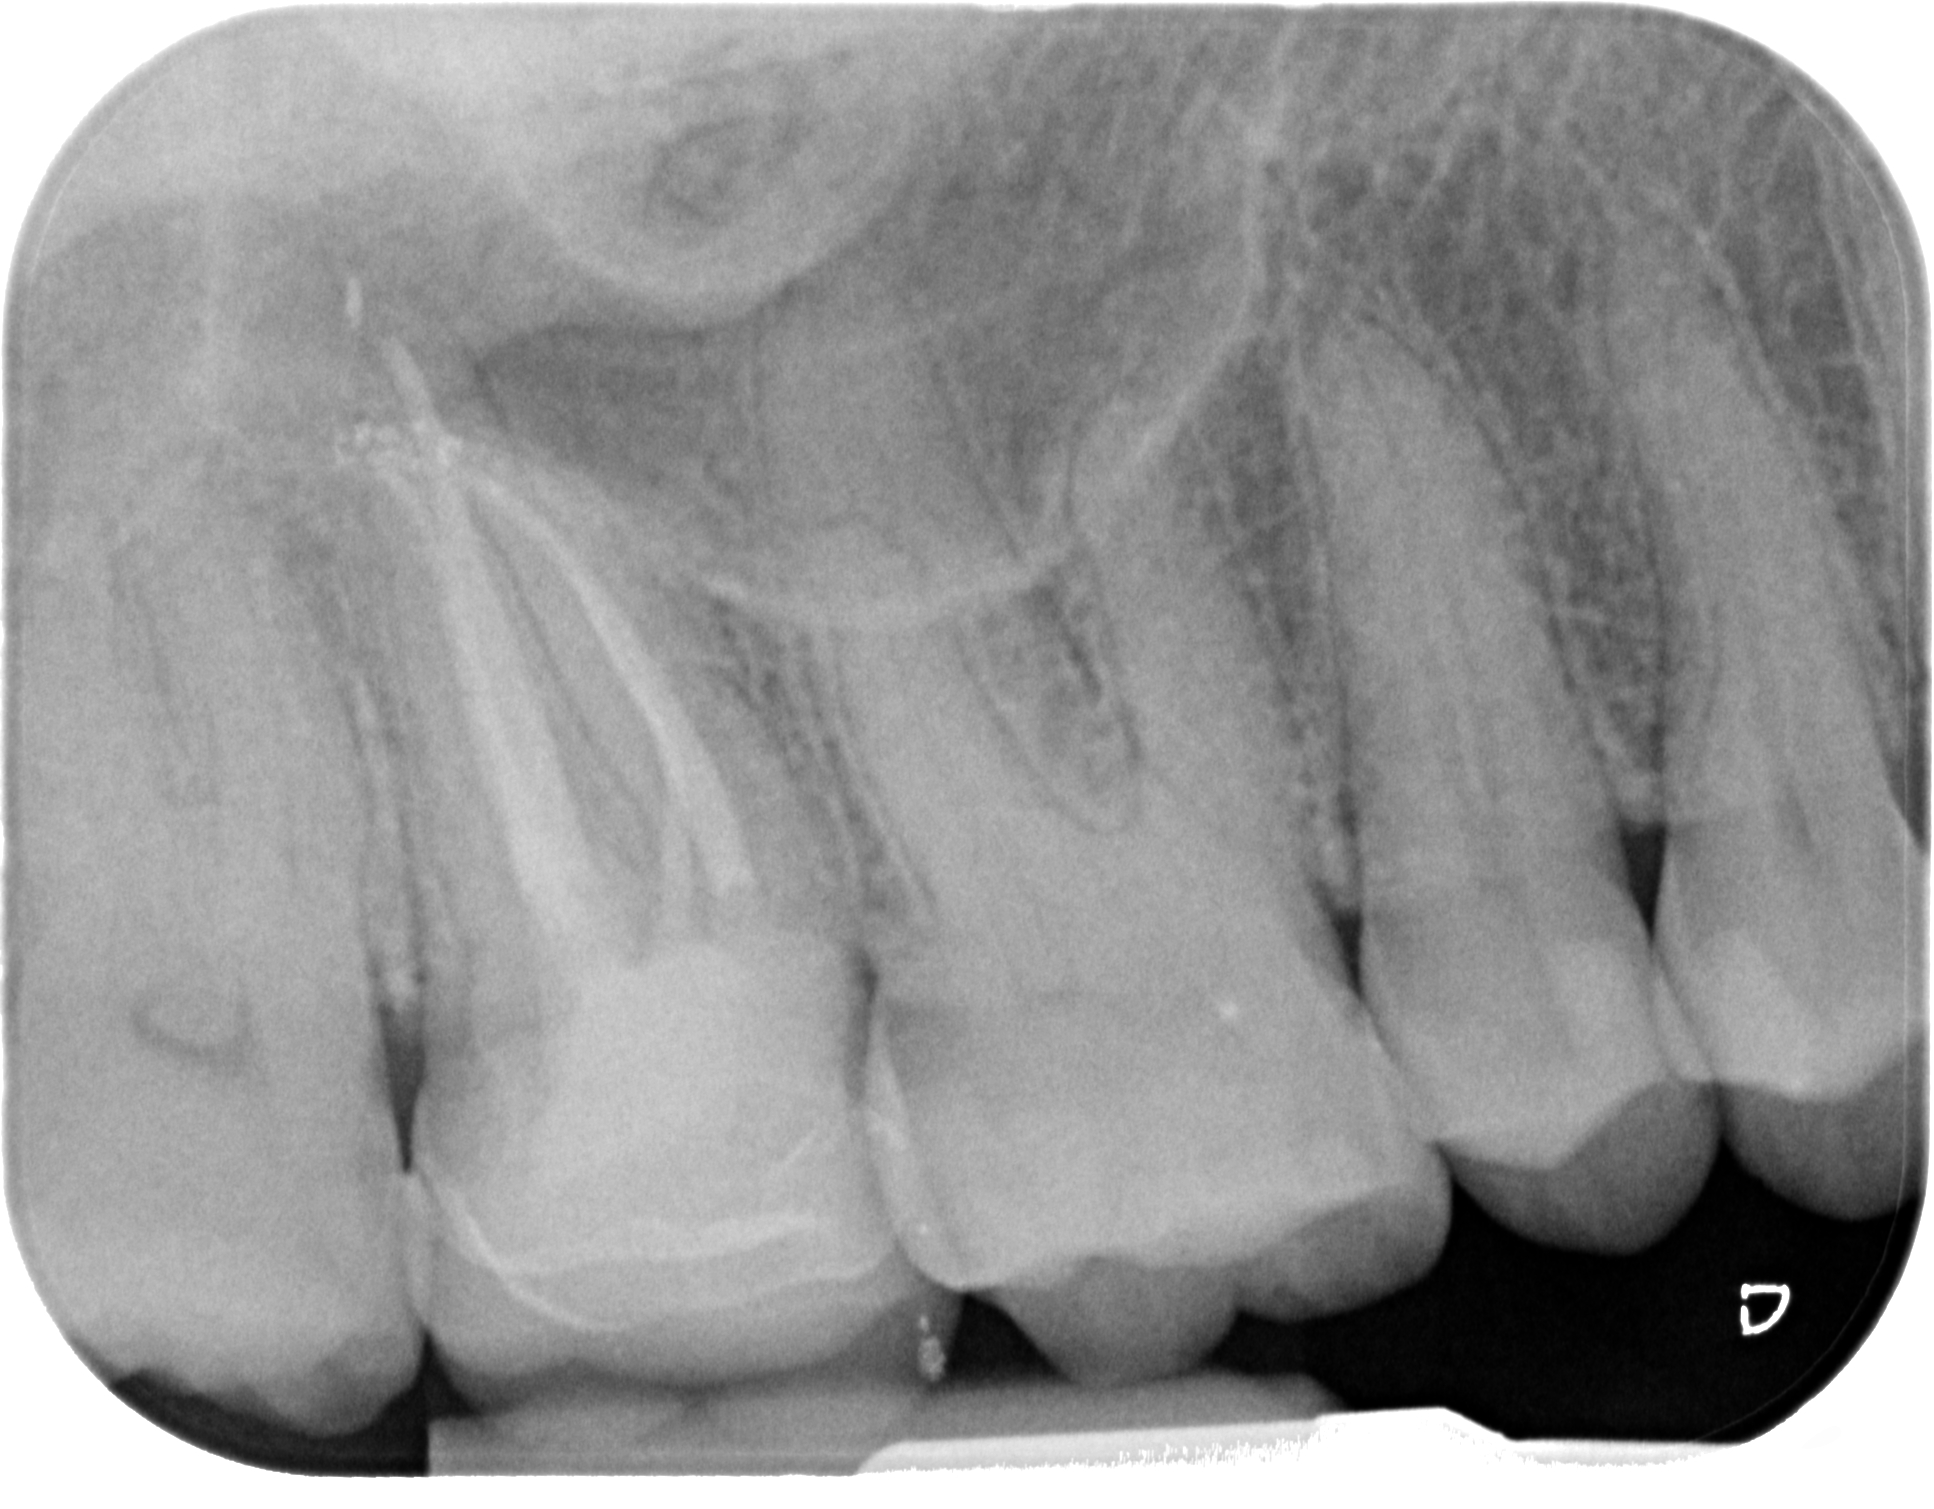

Fig. 4: Canal system shaped and cleaned before obturation.

This refers to the use of a specific type of diamond bur for the penetration step, in particular for maxillary and mandibular molars and maxillary furcated premolars. Deutsch et al. determined morphological measurements concerning the relationship between the occlusal surface and the height and position of the roof and the floor of the pulp chamber in multi-rooted teeth.8, 9 In these teeth, the roof of the pulp chamber is located at the CEJ. In molars, the distance between the top of any cusp and the roof of the pulp chamber is approximately 6.30 mm, and in maxillary furcated premolars, it is 6.94 mm. The pulp chamber of maxillary and mandibular molars has a height of approximately 1.5–2.0 mm, and the average distance from the floor of the chamber to the furcation is approximately 3.0 mm (Table 1; Fig. 13). A more recent publication confirmed these measures employing a micro-CT analysis.10 This means that dentists can rely on plenty of data to approach each root canal therapy in a rational and predictable way.